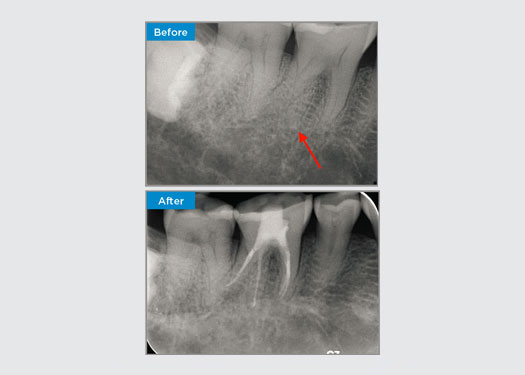

Пациентка 35 лет поступила по направлению специалиста-пародонтолога. Во время первичного эндодонтического обследования пациентка отметила, что два года назад, перед установкой коронки на зуб 16, было проведено удлинение коронки. За два месяца до обращения пациентка отметила припухлость нёбной десны. Врач-стоматолог обнаружил у пациентки 7-миллиметровый пародонтальный карман, прилегающий к небному синусному каналу, связанный с зубом 16. Пациентка была направлена к специалисту-пародонтологу. Специалист-пародонтолог диагностировал первичное эндодонтическое и вторичное пародонтальное поражение. Пациентка удовлетворительно соблюдала гигиену полости рта и регулярно посещала стоматолога. Зуб 16 был чувствителен к перкуссии. Было отмечено, что края коронок были удовлетворительными, а пародонтальные карманы вокруг зуба 16 имели глубину менее 2 мм с буккальной стороны, однако на нёбной поверхности, рядом с синусовым каналом, имелся изолированный пародонтальный карман размером 6,5 мм. Термическое тестирование зуба 16 показало отрицательную реакцию. Зуб 16 имел факторы риска развития апикального периодонтита, такие как отрицательная реакция на термическое тестирование, чувствительность к перкуссии, история глубокой реставрации после операции по удлинению коронки и рентгенографически выявляемое периапикальное заболевание. В анамнезе зуба 16 не было боли при накусывании или жевании, что может свидетельствовать о наличии трещины, сообщающейся с пульпой и/или тканями периодонта. У пациента не было факторов риска развития пародонтологического заболевания, а вокруг других зубов не было аномально глубоких карманов.

Доктор Омар Икрам, Эндодонтист, Кроус Нест, Новый Южный Уэльс, Австралия